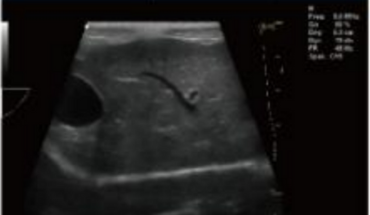

Fonction d'application clinique riche

- Technologie d'imagerie étendue convexe

- Technologie de déviation de réseau linéaire/imagerie trapézoïdale